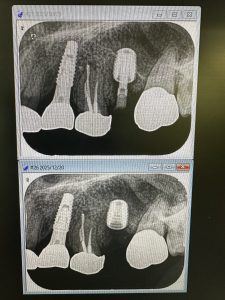

不良肉芽が凄かった方

プラットフォームスイッチングのお陰

皮質骨がシャープになっている 安定